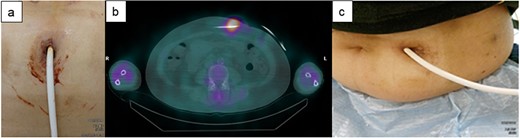

Figure 1 illustrates the concept of the catheter cleaning method via the DLES used in this case series. First, the intravenous indwelling catheter is deeply inserted via the DLES to clean the space around driveline. Then, a cotton swab with 10% silver nitrate solution is used to eliminate infected and contaminated tissues. As adequate removal of the infected tissue is crucial, daily elimination of infected tissue using this procedure is generally continued for 1 week. If the depth of infection space around the driveline is deep and continuous drainage is inadequate, monofilament nylon threads are inserted for continuous drainage of exudate via capillary action. Figure 2 shows how the depth of DLI is assessed and how this procedure is performed in practice. Figure 2a reveals the finding of gallium-67 single-photon emission computed tomography (67Ga SPECT), with a high signal, suggesting that the inflammatory area is inside the DLES. Figure 2a, c present findings of superficial echography examination where hypoechoic areas indicate a space around the driveline; this is the suspected infected area. This procedure is deemed feasible as long as the infected space was within reach of the cotton swab and intravenous catheter from DLES. Figure 2d, e show a cleaning method using an intravenous catheter via the DLES. Similarly, a cotton swab with 10% silver nitrate solution is inserted via the DLES to eliminate infected and contaminated tissues. Monofilament nylon threads are inserted for continuous drainage (Fig. 2f–h).

Evaluation of the depth of DLI. (a) Gallium-67 single-photon emission computed tomography (67Ga SPECT) shows the extent of high signalization from the DLES. (b,c) Body surface echography findings show hypoechoic area around the driveline, suggesting effusion of poorly organized inflammatory fluid from the DLES. (d–f) Cleaning of the driveline tunnel using an intravenous indwelling catheter. The catheter is about 5-cm long; it can be cleaned if the length of the infective driveline tunnel is within reach of the cotton swab and intravenous catheter from DLES. (g, h) The intravenous indwelling catheter may be also useful when the nylon threads are inserted into the driveline tunnel space. A catheter and nylon threads are inserted in the driveline tunnel space. Then, the catheter is removed while leaving the nylon threads. SPECT: single-photon emission computed tomography.